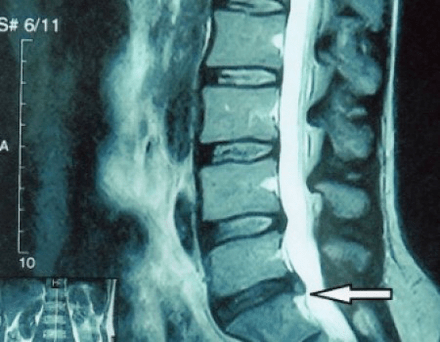

Unha "radiografía" da columna cervical e mesmo as probas funcionais de flexión e extensión non mostran cartilaxe porque o seu tecido permite o paso dos raios X. Non obstante, en función da localización das vértebras, pódense extraer conclusións xerais sobre a altura dos discos intervertebrais, o endereitamento xeral da curvatura fisiolóxica do pescozo - lordose - así como a presenza de crecementos marxinais nas vértebras con irritación prolongada das súas superficies por discos intervertebrais fráxiles e deshidratados. As probas funcionais poden confirmar o diagnóstico de inestabilidade da columna cervical.

Dado que os propios discos intervertebrais só son visibles mediante TC ou resonancia magnética, a resonancia magnética e a tomografía computarizada de raios X están indicadas para aclarar a estrutura interna da cartilaxe e formacións como protuberancias e hernias. Así, coa axuda destes métodos, faise un diagnóstico preciso e o resultado da tomografía é unha indicación e mesmo unha guía real para o tratamento cirúrxico dunha hernia inguinal no departamento de neurocirurxía.